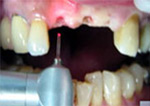

傷口小、免開刀:非傳統翻辦方式,採用最新雷射技術,少流血、少腫痛。以雷射進行植牙療程的主要原因在於:盡量減少植牙區的創傷,以減少病患腫脹、出血及傷口感染機率。 手術時間短:約10分鐘以內完成植體植入。 純熟的技術:條件允許時,可採用現拔現植的方式。 最先進的技巧:講師級的醫療團隊,臨床經驗豐富、效率高。 最頂級的植體:皆有衛生署及FDA許可,術後癒合快,骨整合期縮短。 最精密的瓷牙:不惜成本,一律用貴金屬瓷牙製作,精細程度與真牙極相近。 最優質親切的服務:無菌手術室、術後做雷射穴位止痛消腫、回診服務…等。  |

| (三)以雷射方式進行植牙與傳統方式最大的差異在於: |

以雷射切割傷口後的癒合比傳統方式來得快,且手術區域乾淨,並有助於快速止血。 降低因血液而傳染其他疾病的機會。 可降低手術時的機械性外傷,術後不需縫合,減少結疤程度劑牙托。 雷射操作過程比傳統治療更容易為人接受,在很多方面都比較迅速且有效率,手術後亦較自然舒適。  |